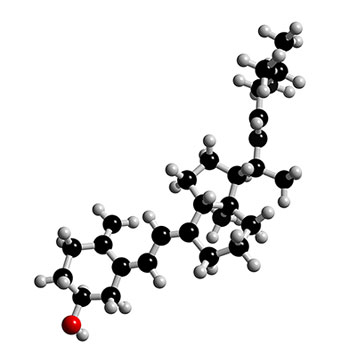

Un nuovo studio, presentato al meeting European Society di Hipertension di Londra, dimostra che l’integrazione di vitamina D può ridurre la pressione sanguigna in pazienti con ipertensione. La vitamina D è importante soprattutto per la salute delle ossa ( è coinvolta nel metabolismo del calcio e del fosforo) ed alla carenza di vitamina D è associata un’ampia gamma di malattie tra cui alcuni tipi di cancro, depressione, diabete, oltre sclerosi e malattia cardiovascolare. Anche se la vitamina D è presente in alcuni alimenti, la maggior parte viene prodotta nella pelle, in reazione alla luce solare. Inoltre la carenza di vitamina D è associata ad alta pressione arteriosa. Un team di ricercatori danesi ha condotto uno studio randomizzato, controllato con placebo, che dimostra che supplementi di vitamina D, possono ridurre la pressione sanguigna, in pazienti ipertesi. La ricerca è stata realizzata su 112 pazienti ipertesi ed ha dimostrato che coloro che hanno assunto vitamina D per 20 settimane, hanno mostrato una significativa riduzione della pressione sistolica centrale. I ricercatori sottolineano che si tratta di un primo studio che quindi deve essere confermato, ma è potenzialmente interessante come parte di una strategia globale per la gestione dell’ipertensione, nei pazienti con bassi livelli di vitamina D.

Integratori di vitamina D possono ridurre la pressione sanguigna in pazienti ipertesi